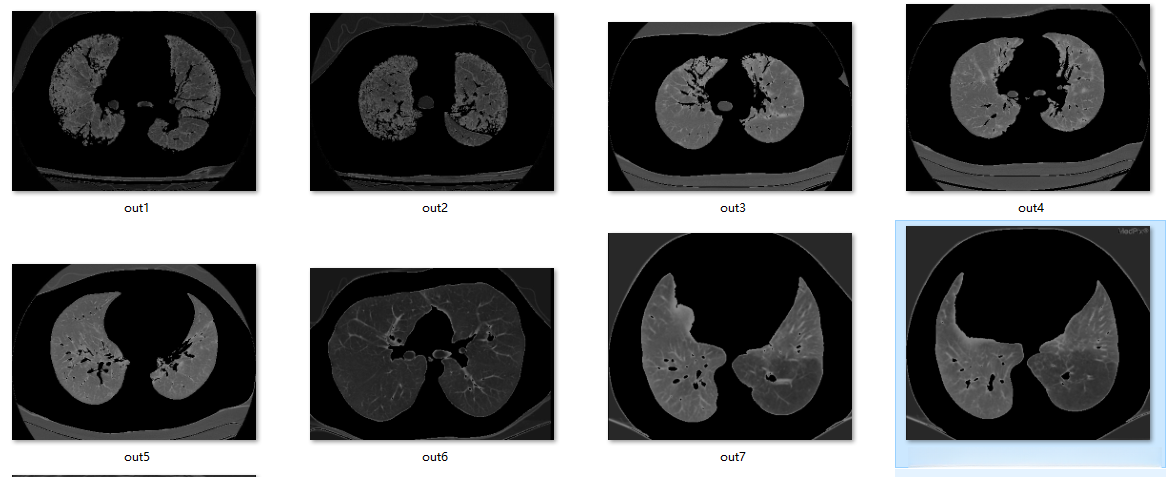

输入:

输出: